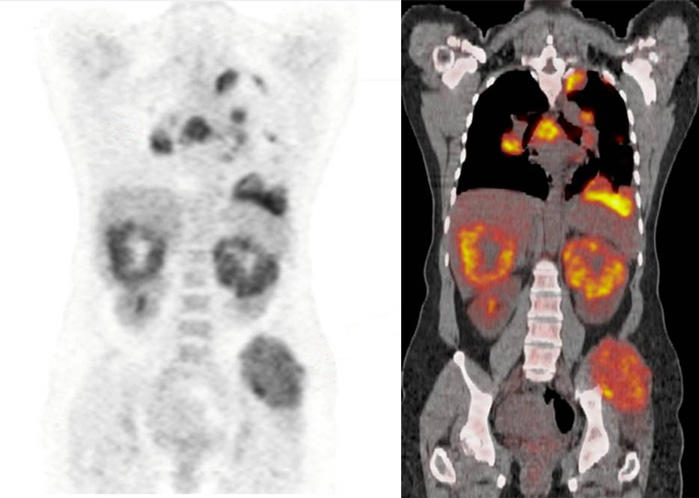

Medical imaging comparison showing a PET scan (left) and PET/CT fusion scan (right) revealing multiple metastatic lesions in a patient with renal cell carcinoma, with orange and yellow areas indicating active cancer sites.

FDG PET/CT scans from a patient with metastatic renal cell carcinoma.

Credit: PLOS One 2016. doi: 10.1371/journal.pone.0153321. CC BY 4.0.